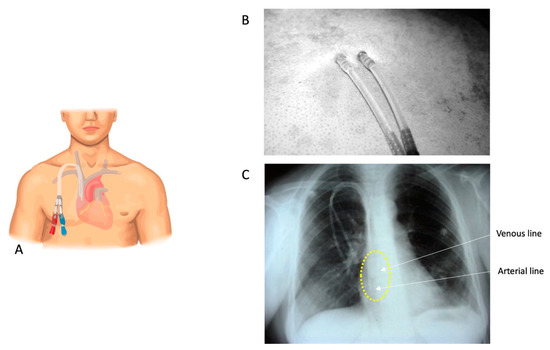

2.4.1. DualCath Looking and Imaging (Figure 1)

- Canaud, B.; Leray-Moragues, H.; Klouche, K.; Morena-Carrere, M.; Chenine, L.; Miller, G.; Cristol, J.P.; Canaud, L. Percutaneous Placement and Management of High-flow Catheter for Hemodialysis: The case for DualCath, two tunneled single lumen silicone catheters. J. Vasc. Access. 2023. [Google Scholar]